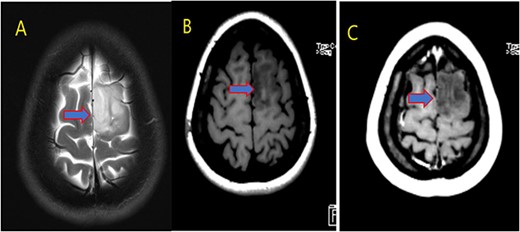

Our patient is a 31-year-old female who presented to the emergency department due to two episodes of generalized tonic colonic seizures. Upon presentation, the patient was administered with supplemental oxygen. She was drowsy and confused while exhibiting signs of right-sided hemiparesis and paralysis. Her pupils were 3 mm and reacted briskly while she showed good left-sided localizing. Her seizures terminated after intravenous administration of midazolam at 5 mg. Further, it was known that she has been symptomatic for 1 month and had been suffering from episodes of seizures, with shaking and tremors of upper limbs, and brief episodes of blackouts for about a minute. These episodes were associated with headache and nausea but were self-limited. Seizures recurred two to three times per week. She denied any fall, tongue bite, loss of consciousness, and limb weakness or numbness. A computerized tomography (CT) scan was suggested, which showed left high parietal hypodensity with vasogenic edema (Fig. 1). She was recommended Keppra 1.5 g and dexamethasone 12 mg. Further, a contrast MRI of the brain was performed (Fig. 2). After a thorough evaluation of the patient’s medical records and current condition, it was decided to proceed with an excision of the tumor using the AC technique. To foster trust and comfort, the same anesthesia and surgical teams were assigned to the patient. Before the procedure, the patient was fully informed about the nature of the procedure and the possibility of a failed outcome or further need for a conversion to general anesthesia. To assess the patient’s cognitive and language abilities, preagreed questions and exercises were performed. These included memory-related queries, such as asking for the patient’s phone number and the names of her dog, and motor commands, such as squeezing a squeaky toy. The patient was prepared for awake navigator-assisted left frontal craniotomy for excision of the left frontal lobe space-occupying lesion, which was suspected to be either a low-grade glioma or fibrous dysplasia. During the surgical procedure, a central line was placed in the right jugular vein using ultrasound, followed by the insertion of a right radial arterial line, a urinary catheter, and two additional venous lines. The patient received a continuous flow of 4–6 l of oxygen per minute. To achieve conscious sedation, the patient received infusions of remifentanil and propofol at varying rates. The patient underwent a 5-hour surgical procedure to remove a tumor. During the procedure, the patient was under sedation and was regularly tested for response to predetermined commands. Her conscious sedation level fluctuated, but she never lost consciousness. The removal of the tumor was successful, and postoperative examination revealed normal motor function and cranial nerve function. The patient was taken to the intensive care unit, and postoperative MRI showed a reduction in the size of the mass lesion in the left frontal lobe/superior frontal gyrus along with mild vasogenic edema surrounding it (Fig. 3).

MRI brain with contrast (A) T2, (B) FLAIR, and (C) T1 postcontrast; in comparison to the fore mentioned study; still noted postoperative changes in the form of craniotomy (regression of size of space occupying cortical mass lesion with mild surrounding vasogenic edema in the left frontal lobe/superior frontal gyrus).